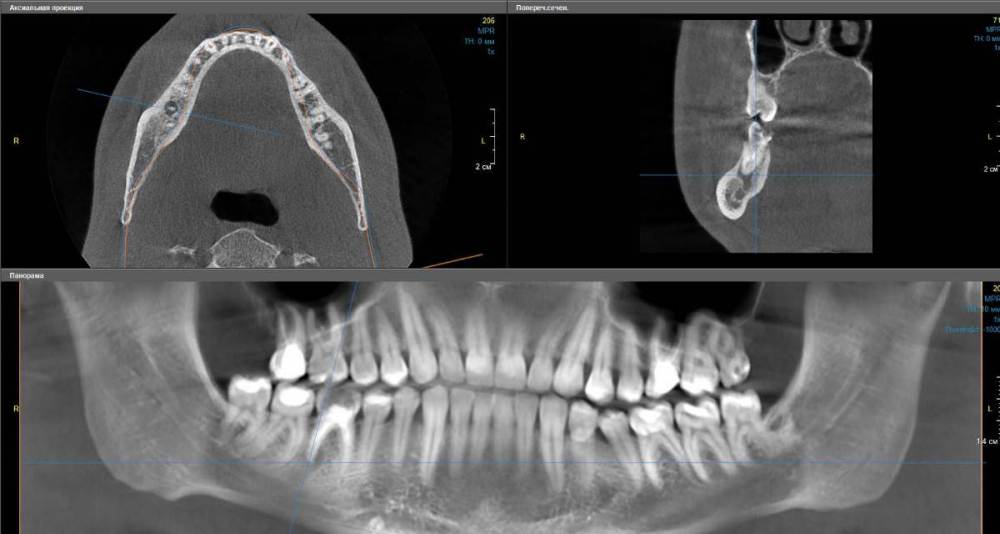

Artooth Опубликовано 9 июля, 2022 Поделиться Опубликовано 9 июля, 2022 (изменено) Правая нижняя шестерка (46), зуб был депульпирован более десяти лет назад, даже сложно вспомнить точно, насколько давно. Сам зуб сейчас выглядит так (см. первое изображение), пломба тёмно-бежевого цвета, в районе десны со стороны щеки у шейки почернение. Сам зуб не болит, десна тоже, при постукивании реакции нет, вообще никаких видимых симптомов. На КТ под корнем виднеется полость (см. второе и третье изображения). Хотя при этом похожая полость есть и ниже. На другой стороне челюсти в этом месте вообще все пространство в виде подобной полости. Не совсем понятно. Возможно наверняка определить, что зуб был депульпирован резорцин-формалиновым методом? Похоже ли, что идет развитие периодонтита и стоит ли бить тревогу? Изменено 9 июля, 2022 пользователем Artooth Ссылка на комментарий